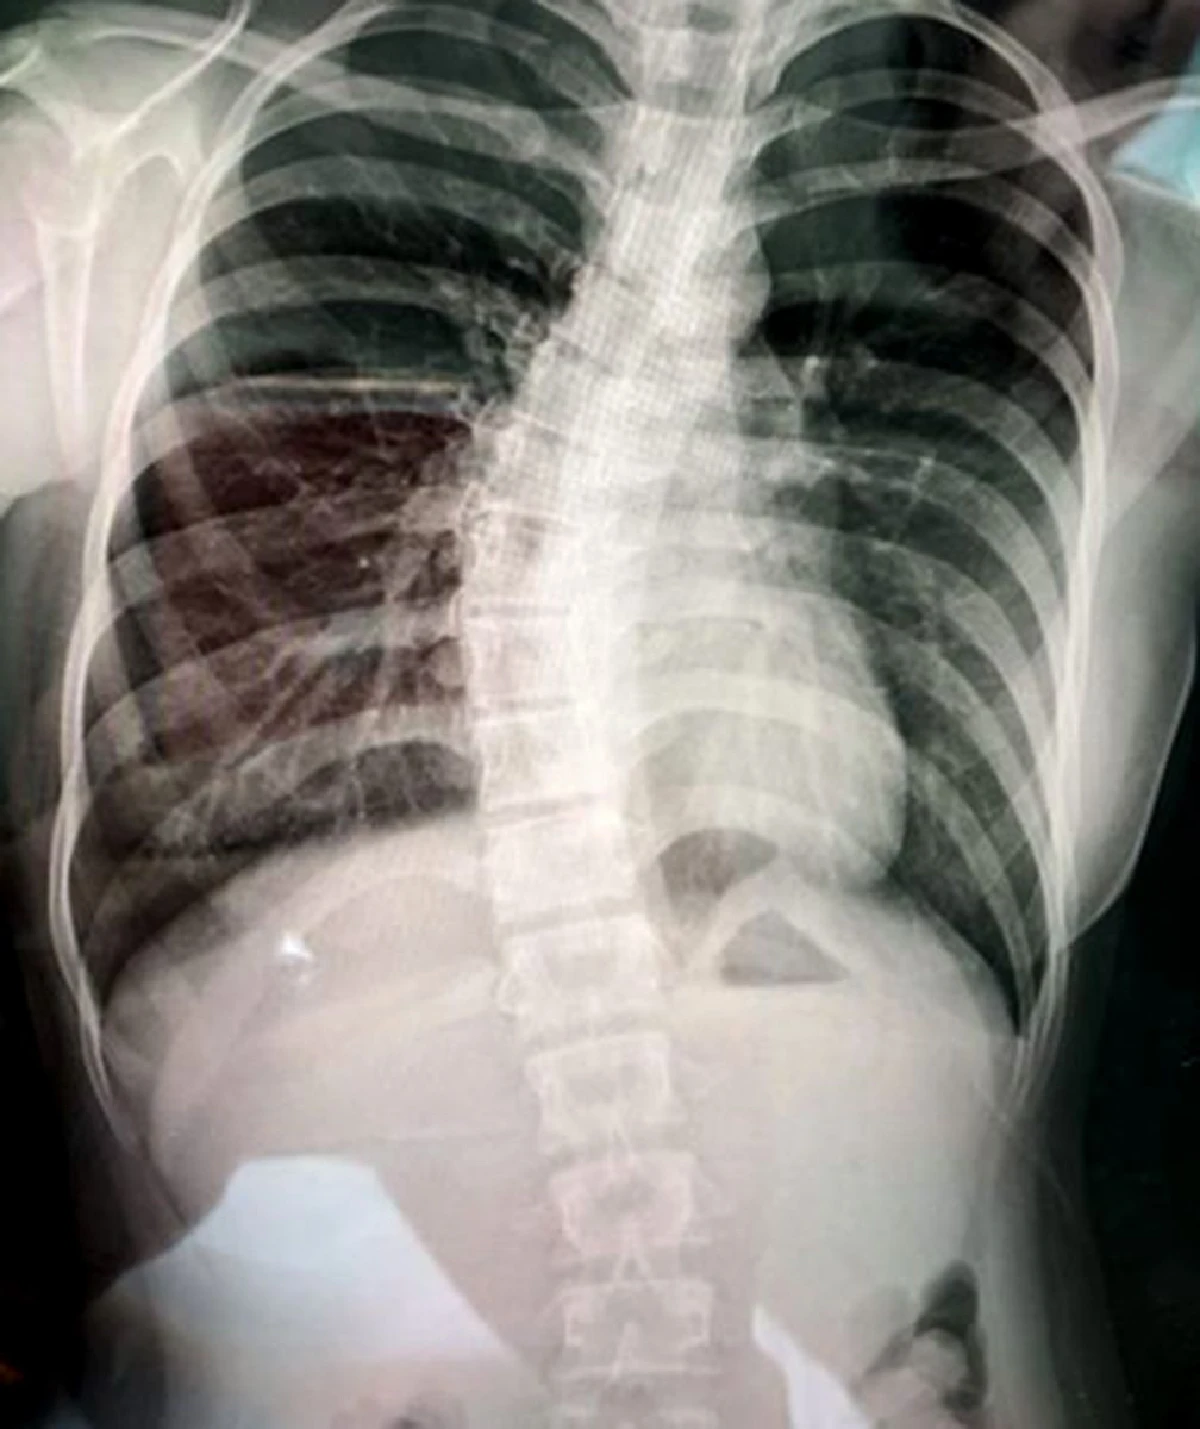

กระดูกสันหลังคด (Scoliosis) คือการคดงอของกระดูกสันหลัง หรือมีลักษณะบิดเบี้ยวไปด้านข้าง ทำให้เสียสมดุลและไม่สวยงาม ซึ่งเกิดขึ้นได้กับทุกวัย แต่ส่วนใหญ่แล้วมักเกิดขึ้นกับเด็กที่มีอายุตั้งแต่ 10-15 ปี ซึ่งมักคดไม่มาก และไม่ทำให้รู้สึกเจ็บ หากอาการไม่รุนแรงมักไม่ต้องเข้ารับการรักษา แต่หากกระดูกสันหลังคดมาก อาจทำให้มีอาการปวดหลัง หรือรู้สึกเหนื่อยง่าย รวมทั้งมีอาการแทรกซ้อนอื่นๆ ตามมา ซึ่งจากการวิจัยพบว่าเด็กไทยมีกระดูกสันหลังคดในอัตรา 1 ต่อ 10,000 คน แต่ระยะหลังพบเด็กเป็นโรคนี้มากขึ้น ซึ่งผลกระทบต่อสุขภาพ ได้แก่ ทำให้แนวสะโพกเอียง รูปร่างพิการ ปวดหลัง มีปัญหาทางระบบหายใจ หอบเหนื่อยง่าย เป็นโรคปอดบวม ปอดอักเสบ หัวใจทำงานหนักจนสามารถเกิดภาวะหัวใจล้มเหลวได้

ส่วนในรายที่กระดูกสันหลังคดเกิน 50 องศาของการคดนั้น จะพบว่าปุ่มนูนกลางกระดูกสันหลังมีการบิดหมุนดูไม่เท่ากันไปทั้งแนวกระดูกสันหลัง และมีอาการเหนื่อยง่าย หอบ เนื่องจากการที่กระดูกสันหลังคด ทำให้กระดูกซี่โครงไปกดเบียดโพรงในช่องปอดให้เล็กลง ปอดจึงขยายตัวได้ไม่เต็มที่ ความจุปอดจึงลดลง